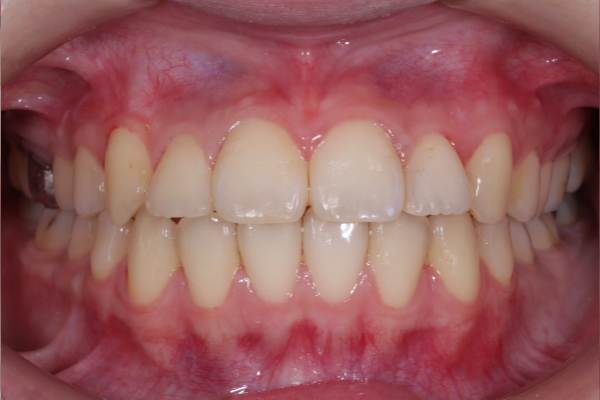

AFTER

本症例では適切なタイミングで診断と介入を行えたことで、矯正的牽引により永久犬歯を歯列内へ誘導することができました。

犬歯は咬合誘導および審美性に重要な役割を担う歯であり、早期の診断が将来的な咬合安定につながります。

今後は保定管理および定期的な経過観察を行っていきます。